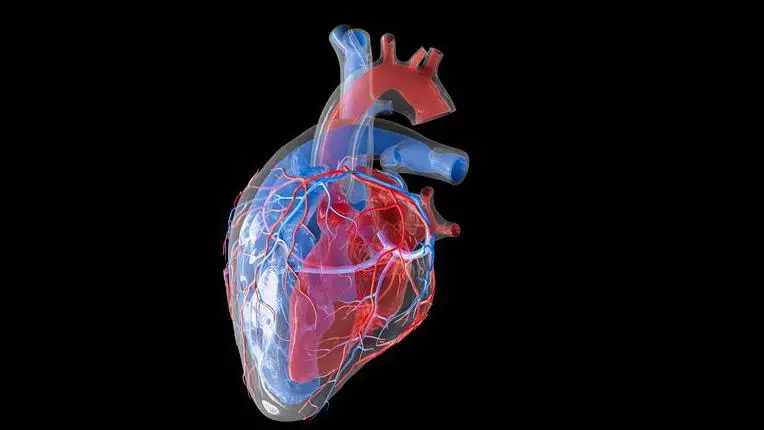

MANAUS (AM) – A arritmia cardíaca é uma condição que afeta o ritmo do coração e pode causar falta de oxigenação no cérebro, levando a danos irreversíveis em poucos minutos. Os sintomas podem incluir fraqueza, tontura e desmaio.

As arritmias cardíacas podem se manifestar de três maneiras: quando o coração bate muito devagar (bradicardia), quando bate rápido demais (taquicardia) ou quando bate de forma irregular (fibrilação atrial, flutter atrial e extrassístoles ventriculares, entre outras condições).

“As arritmias podem ser classificadas de acordo com a parte do coração afetada, a frequência cardíaca e o mecanismo desencadeante. Algumas se manifestam de maneira silenciosa”, informou o especialista José Cotta.